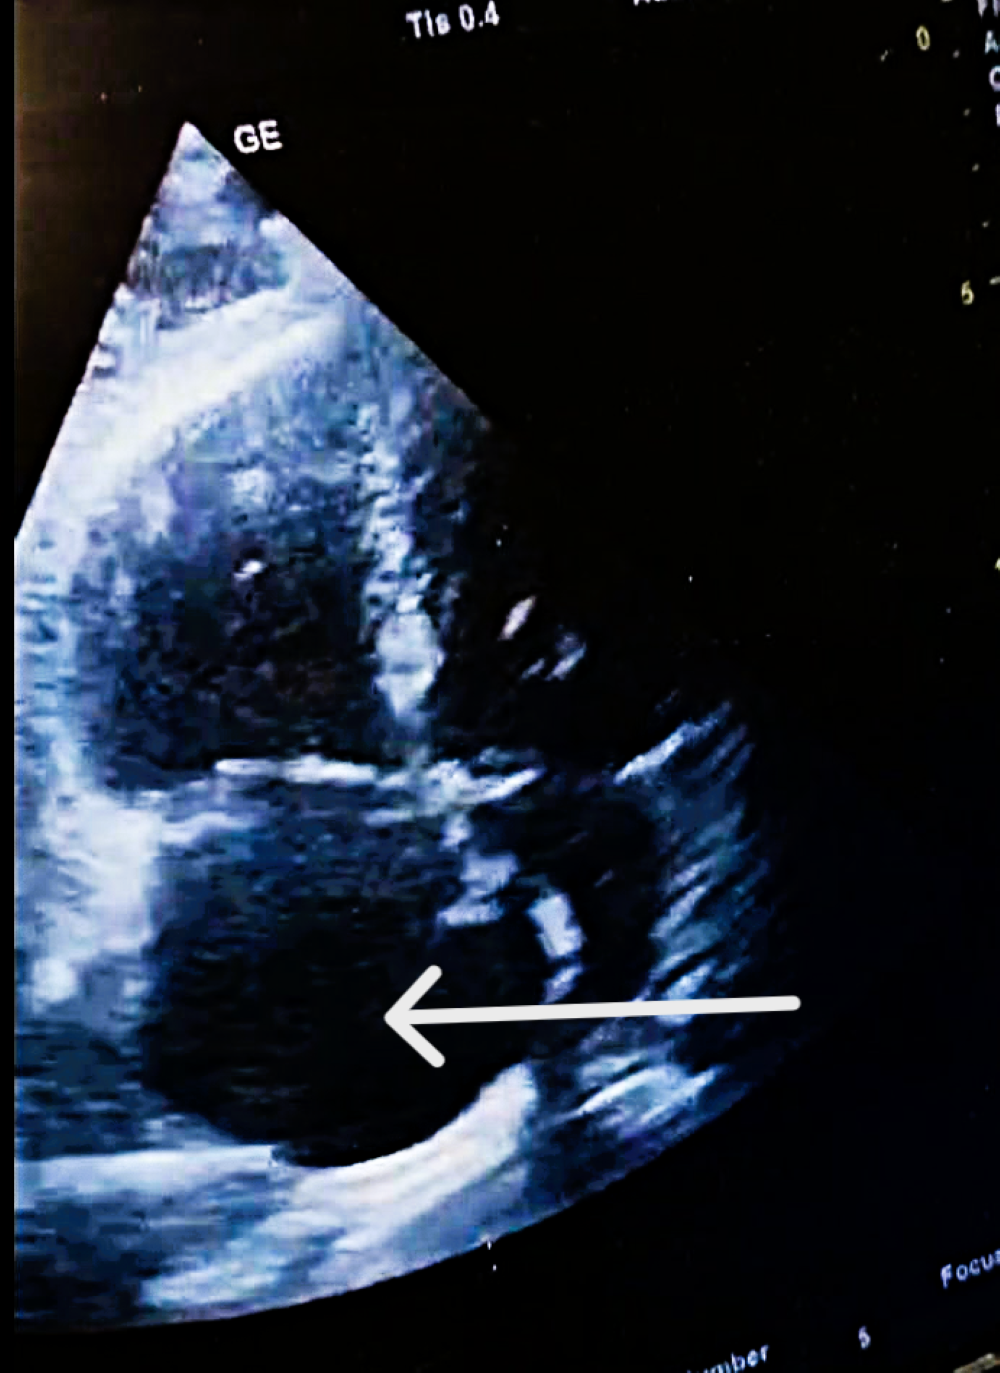

| Mobile RA thrombus | Large, serpentine, prolapsing through tricuspid | High embolic risk |

| Thrombus mobility | Free-floating, unstable | High embolization potential |

| POCUS-TTE—Parameters, Values and Risk Classification | |||

| RV/LV ratio | 1.39 | high | Intermediate-high-risk |

| TAPSE (mm) | 12 | low | Intermediate-high-risk |